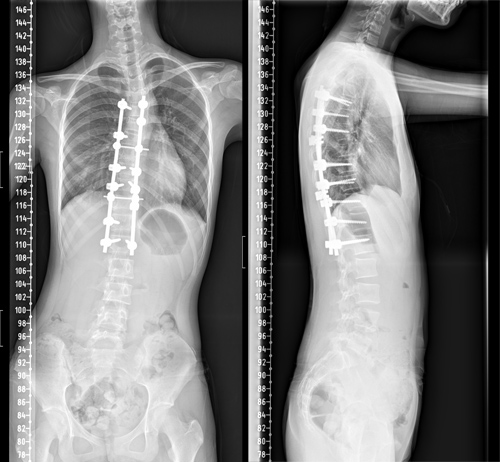

13岁女孩脊柱畸形 手术矫正“罗锅”增高4.5cm

患者小冰今年13岁,4个月前家属发现小冰肩背部明显不对称,严重影响美观,且无法平卧入睡,经多方咨询,慕名来临床医学院/附属医院骨三科就诊。专科检查发现患者脊柱呈明显S型弯曲,躯干向右侧倾斜,双肩不等高,剃刀背畸形,主胸弯Cobb角度达60°,脊柱畸形较为严重。该院骨三科朱述浪主任带领脊柱外科团队,详细讨论了小冰的病情。

骨三科脊柱外科医护团队与麻醉科、手术室等进行了充分的术前讨论,制定周密的麻醉及手术方案。由朱述浪主任主刀,黄波副主任医师及汪智文医师共同为患者实施了后路脊柱侧弯矫形+胸廓成型手术,手术当中采用间接去旋转+多节段Ponte截骨松解技术。为了减少异体血的输入,术中采用了自体血回输,还使用了神经电生理监测为手术保驾护航,将术中置钉过程中可能损伤脊髓或神经根的风险降到最低。经过4个多小时的艰苦奋战,手术顺利完成。

术后护理团队制定了详细的护理计划,严密观察患者生命体征及切口情况。在科室全体医护人员的共同努力下,小冰术后各项指标恢复良好,术后68小时便拔除引流管,并佩戴支具下床活动。复查脊柱全长片提示脊柱S型弯曲得到了充分矫正,双肩等高,剃刀背畸形消失。术后,小冰终于可以正常平卧睡觉,而且身高达到164.5cm,较术前足足增高了4.5cm。